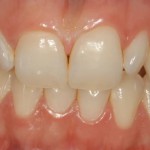

Faccette in ceramica integrale

Faccette in ceramica integrale: preparazione e fase protesica provvisoria Il dottor Coraini ripercorre in tre video le fasi fondamentali per la realizzazione di due faccette...